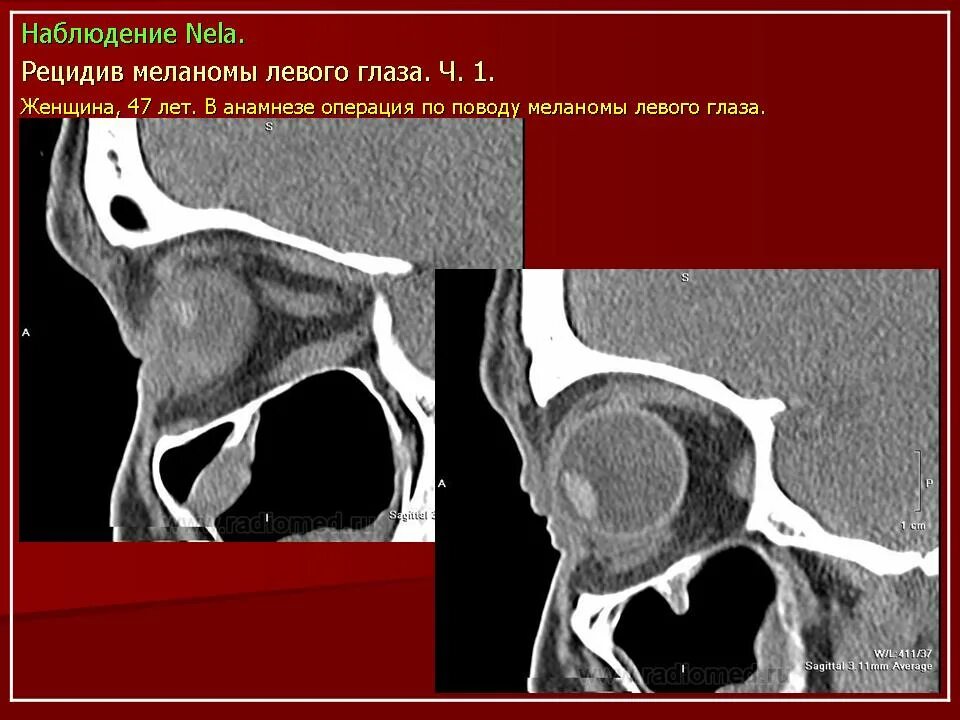

Данные кт